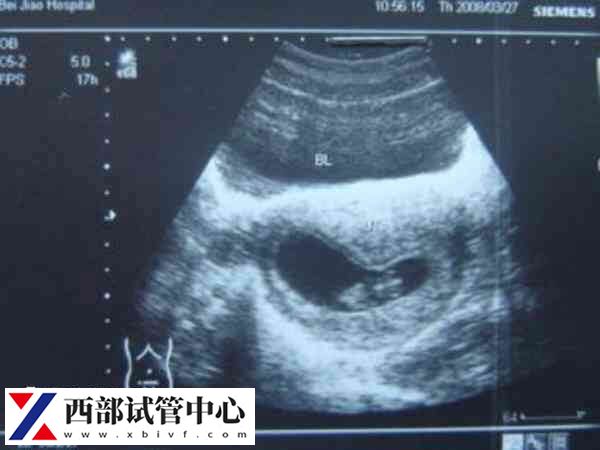

刚开始怀孕差不多50天左右,需要通过B超检查受精卵到底是长在宫内,还是宫外,这个时期的b超检查时非常关键的。因为如果是宫外孕,将会引起大出血、威胁到孕妇的生命体征,如果确认在宫内又能够看到胎心,那么胎儿就可以继续生长发育。

怀孕22至26周这个时候应该说是看到宝贝最好的时机,医生会做一次完整的胎儿结构筛查,从头到脚采集宝宝的很多图像,仔细观察是否有重大问题。要做好这次检查,需要天时地利人和—医生有技巧,宝宝要配合。宝宝最好是醒着能活动,不要趴着睡,或最好是脸朝医生睡。医生如果觉得宝宝在准妈妈肚子里不动,会让准妈妈出去转一圈、散个步回来,等着宝宝翻个身再来看。所以可能检查时间会比较久,这是为了检查的更加准确和完整。